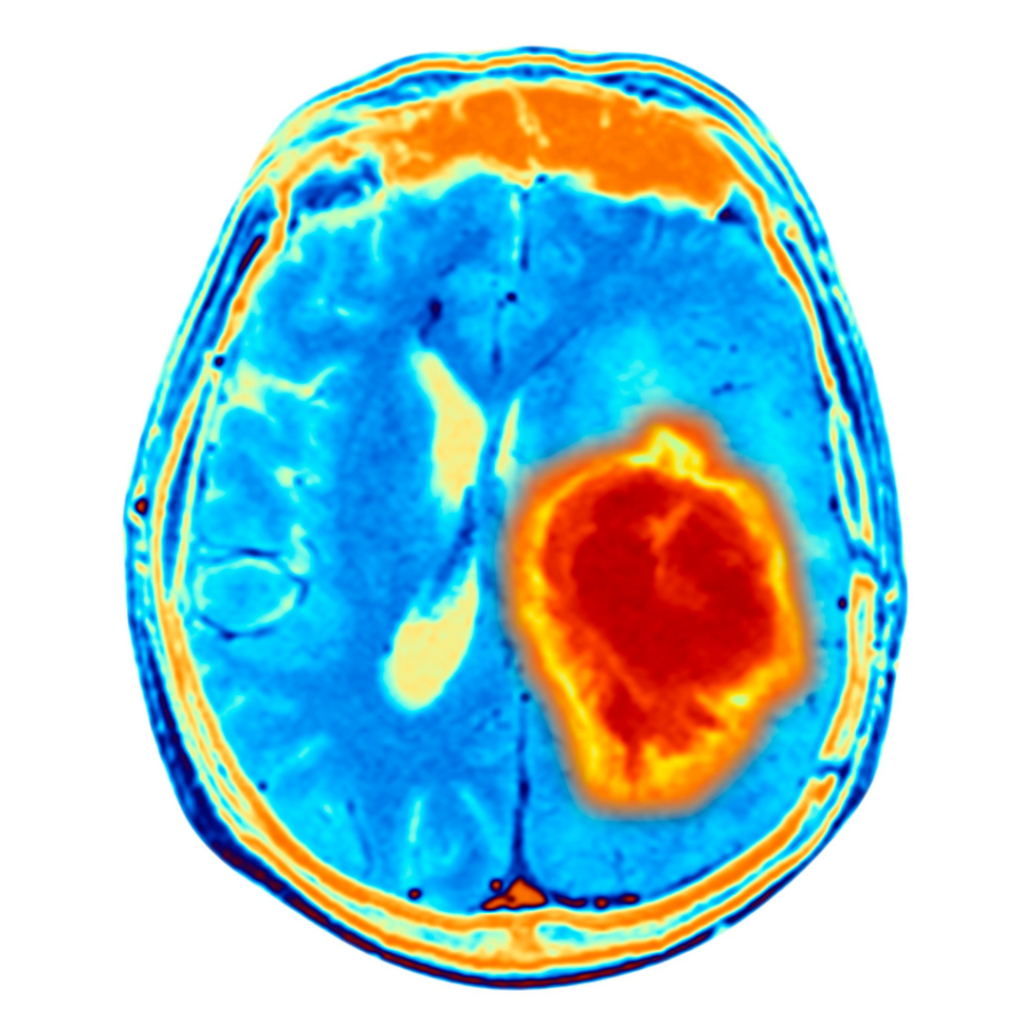

Trata-se de um estudo multicêntrico e randomizado envolvendo pacientes com hemorragia intracerebral espontânea supratentorial, onde foi avaliado o tratamento cirúrgico versus o tratamento clínico isolado.  Foram incluídos pacientes com hemorragia lobar ou ganglionar basal anterior com volume 30 a 80 ml, na proporção de 1:1, dentro 24 horas após a última vez que se soube que estavam bem, para remoção cirúrgica “minimamente invasiva” do hematoma mais tratamento médico baseado em diretrizes (grupo cirúrgico) ou apenas ao manejo médico baseado em diretrizes (grupo controle). O desfecho primário de eficácia foi a pontuação média no teste ponderado pela utilidade da escala de Rankin modificada (variação de 0 a 1, com pontuações mais altas indicando melhores resultados, de acordo com avaliação dos pacientes) aos 180 dias. O ensaio incluiu regras para adaptação dos critérios de inscrição com base na localização da hemorragia. O desfecho primário de segurança foi a mortalidade em 30 dias.

Foram incluídos 300 pacientes com hemorragia intracerebral espontânea supratentorial, dos quais 30,7% localizavam-se nos gânglios basais anteriores, e 69,3% eram lobares.  Após a inclusão de 175 pacientes, uma regra de adaptação foi acionada e apenas pessoas com hemorragias lobares foram incluídos. A pontuação média na escala de Rankin modificada ponderada pela utilidade em 180 dias foi de 0,458 no grupo de cirurgia e 0,374 no grupo de controle (diferença, 0,084; Intervalo de credibilidade bayesiano de 95%, 0,005 a 0,163; probabilidade posterior de superioridade de cirurgia, 0,981). A diferença média entre o grupo cirúrgico e controle  foi de 0,127 (95% Bayesian intervalo de credibilidade, 0,035 a 0,219) nos pacientes com hemorragias lobares e −0,013 (intervalo de credibilidade bayesiano de 95%, −0,147 a 0,116) nos pacientes com hemorragia ganglionar anterior. A mortalidade em 30 dias foi 9,3% no grupo cirúrgico e 18,0% no grupo controle. Cinco pacientes (3,3%) do grupo cirúrgico apresentaram ressangramento pós-operatório e piora neurológica.

Nos pacientes com hemorragia intracerebral espontânea supratentorial lobares, o tratamento cirúrgico minimamente invasivo realizado dentro de 24 horas resultou num melhor resultado funcional em 180 dias comparado a tratamento clínico exclusivo.1